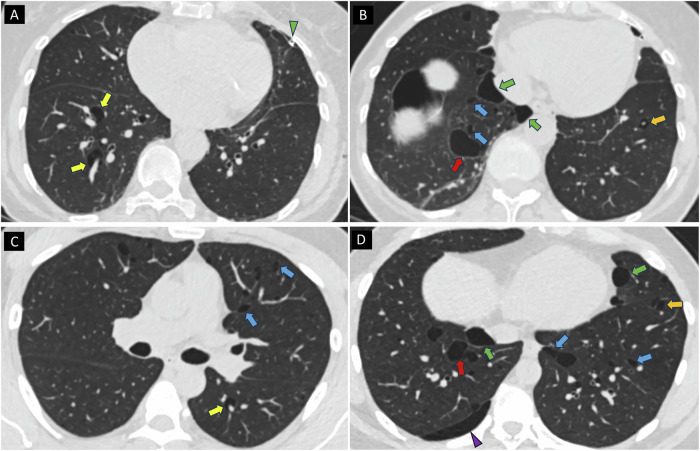

Results: Of 1475 patients with RN, 127 (8.6%) had PCs; 40 underwent genetic testing (median age 56 [49-68], 28 men), and 6/127 (4.7%) individuals tested positive for BHDS. BHD+ had significantly more and larger cysts, affecting more lobes (p < 0.01). Higher prevalence of PCs with a perivascular (100% vs. 37%; p = 0.01) and interlobular septal location (100% vs. 16%; p < 0.001), and perilymphatic distribution (100% vs. 5%; p < 0.001) was found in BHD+. All BHD+ had elliptical, irregular, and variable shape PCs, compared to a lower prevalence of these in BHD- (p < 0.01). Traversing vein sign was more common in BHD+ (83% vs. 24%; p = 0.01). The highest accuracy was achieved for perilymphatic distribution (97%), followed by irregular shape (94%) and interlobular septal location (91%).

Key points: Birt-Hogg-Dubé syndrome (BHDS) should be considered in patients with renal neoplasms and multiple pulmonary cysts. A lower zone predominant, perilymphatic distribution of pulmonary cysts is a strong indicator of BHDS. Identifying specific CT features of pulmonary cysts can improve recognition of BHDS.